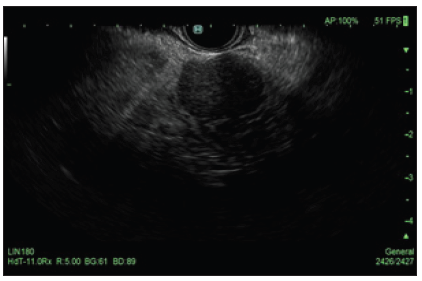

71-year-old African American woman recently diagnosed with poorly differentiated invasive ductal carcinoma of the left breast was found to have a 2cm left adrenal nodule on abdominal CT scan raising concern for metastasis (Figure 1). While the patient remained largely asymptomatic, discussion at our institution’s Multidisciplinary Tumor Board resulted in continued suspicion for a metastatic process. The gastroenterology team was then involved, and an EUS was conducted, revealing a round hypoechoic lesion in the left adrenal gland (Figure 2). FNA for cytology was successfully performed with cytology results being negative for malignant cells. Further, immunohistochemical staining confirmed benign adrenocortical tissue (Figure 3).

Figure 2: A round hypoechoic mass was identified endosonographically in the left adrenal gland. The mass measured 25mm in maximal cross-sectional diameter. Borders were well-defined.